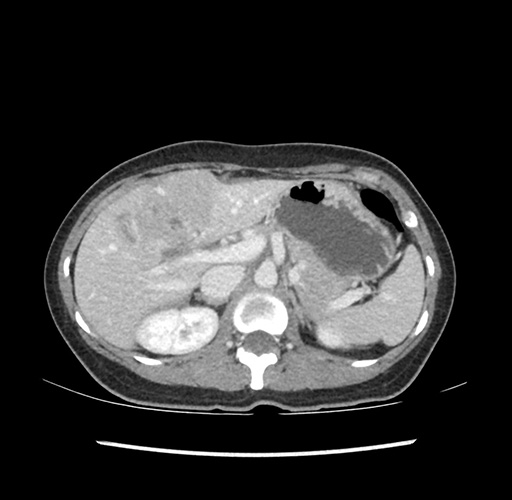

Imaging Analysis

Look through the patient's CT scan to identify any areas of concern for the necessary procedure.

Based on your CT findings, which issue(s) would give reason for "planned slowing down moment(s)" in this case?